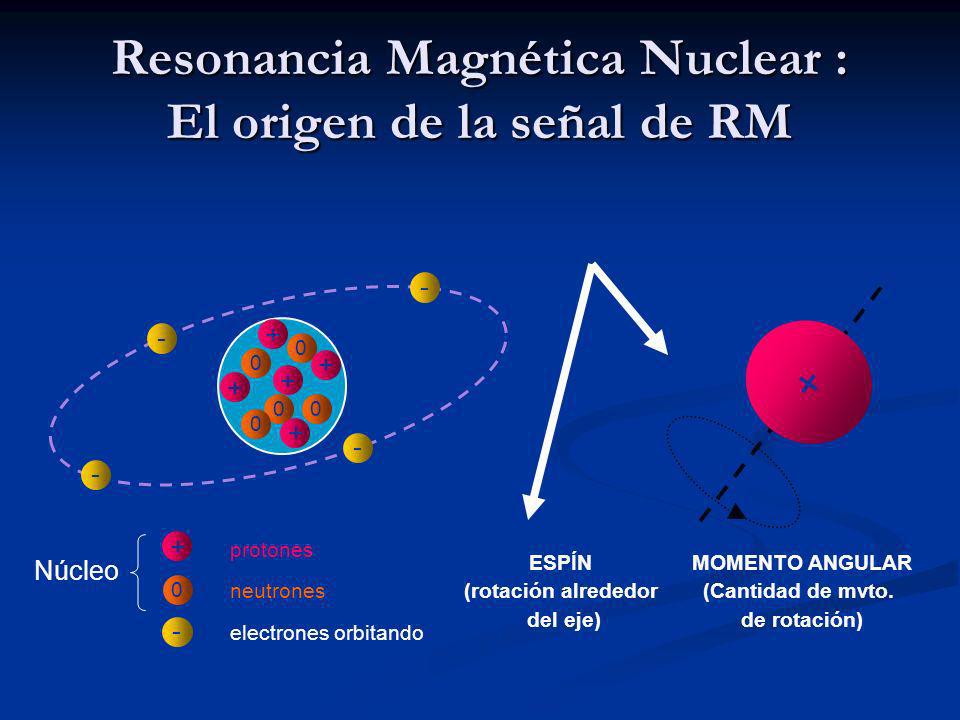

La resonancia magnética nuclear, o RMN, es un método para producir imágenes detalladas de los órganos y tejidos a lo largo del cuerpo sin la necesidad de usar rayos X o radiación "ionizante". En cambio, la RMN utiliza un poderoso campo magnético, ondas de radio, campos magnéticos que cambian rápidamente y una computadora para crear imágenes que muestran si está presente alguna lesión, enfermedad o condición anormal.

¿Cómo funciona?

Para realizar una RMN, el paciente es ubicado adentro de la máquina de RMN, que por lo general es un aparato grande con forma de dona abierto en ambos extremos. El poderoso campo magnético alinea las partículas atómicas llamadas protones que existen en la mayoría de los tejidos del cuerpo. Entonces, las ondas de radio aplicadas hacen que estos protones produzcan señales que son detectadas por un receptor dentro del aparato.

El campo magnético rápidamente cambiante otorga a estas señales características específicas y, con la ayuda del procesado por computadora, se crean imágenes de los tejidos, en forma de "rodajas" o "rebanadas", que se pueden ver en cualquier orientación.